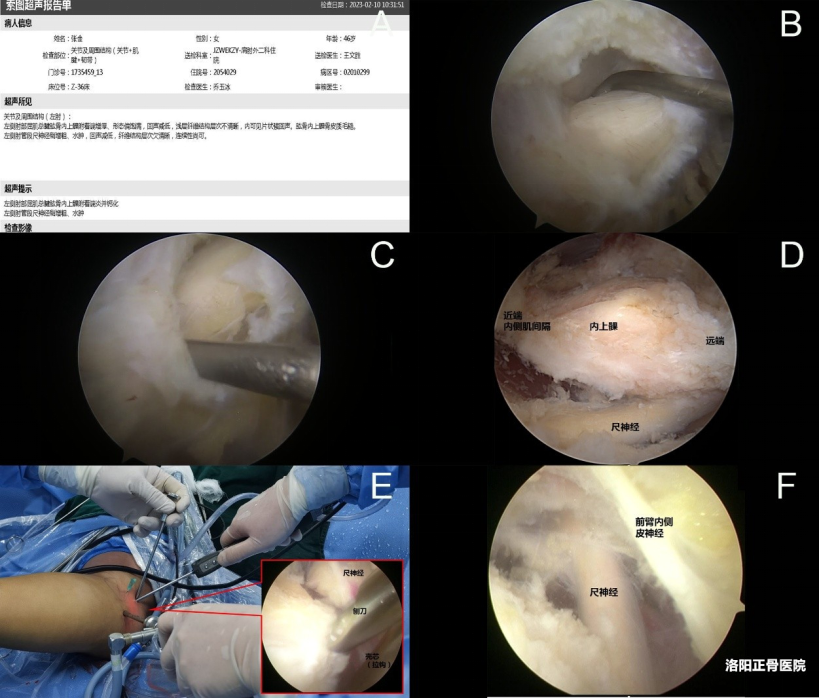

6. 尺神经探查松解:兼顾并发症处理

对于合并尺神经卡压的Ⅱ型患者,需在清理病变后进一步松解尺神经。通过射频设备紧贴内上髁后方剥离肘尺管支持带,清除尺神经沟内的骨性占位或软组织粘连,全程避免干扰尺神经基底部组织,保持尺神经稳定性。

操作关键:松解范围以解除卡压为目标,避免过度游离影响神经血供。

图注:术前超声确认病变部位和尺神经情况,切除部分肘管支持带,向近端松解肘关节支持带以进一步松解尺神经,完全显露内上髁和其后方的尺神经,鞘芯自近端入路插入向后侧剥离保护尺神经下清理内上髁,尺神经松解后可见表浅走行的前臂内侧皮神经